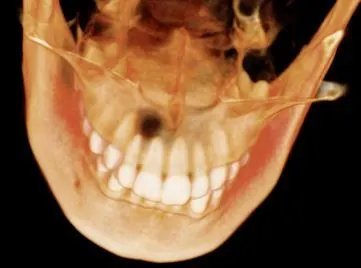

Case 2